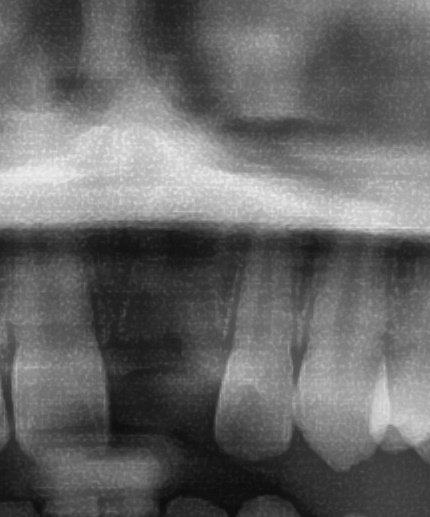

今回の患者様はインプラント植立を希望され、左上1番目の植立が決まりました。

しっかりとインプラント埋め込まれた後は、動揺がないか、噛んだ時に当たらないかなどを確認して、最後にパノラマ写真を撮影して今回のオペは終了となりました。